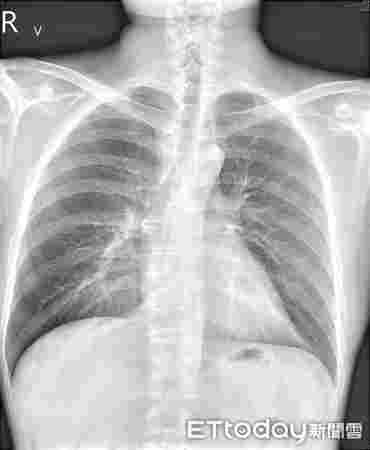

在短短幾個月的時間里,該男子開始出現咳嗽、氣喘、痰多、呼吸困難等呼吸道癥狀,以及全身皮膚干燥瘙癢的嚴重過敏反應。 他最近因懷疑電子香煙引起過敏反應而住進臺北一家醫院。

治療這名電子煙用戶的蘇一峰醫生告訴記者,該患者在開始吸電子煙之前,頭部出現了局部牛皮癬,但在開始吸電子煙后,癥狀惡化,最終全身出現了嚴重的牛皮癬。

但皮膚病只是問題的一部分,這位臺灣醫生補充說,他的病人還患有哮喘,被診斷為肺炎,他的血液檢查也顯示他的過敏指數飆升。 聽他這么說,都是因為那些討厭的電子煙。

這位臺灣醫生說,這位未透露姓名的患者停止使用電子煙,并接受了特殊治療,以抑制他對電子煙加劇的免疫反應,哮喘和牛皮癬等癥狀都得到了改善。